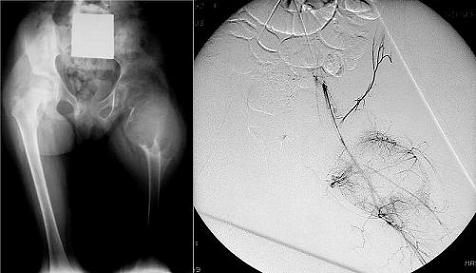

Sequenza di radiografie illustranti la fase intermedia di ristrutturazione ossea della lesione dopo l'embolizzazione.

Embolizzazione curativa: Sequenza di radiografie illustranti la fase intermedia di ristrutturazione ossea della lesione dopo l'embolizzazione.

Situazione pre-embolizzazione (radiografia a sinistra) e fase di guarigione a 2 anni dall'embolizzazione (radiografia a destra).

Embolizzazione curativa: Situazione pre-embolizzazione (radiografia a sinistra) e fase di guarigione a 2 anni dall'embolizzazione (radiografia a destra).